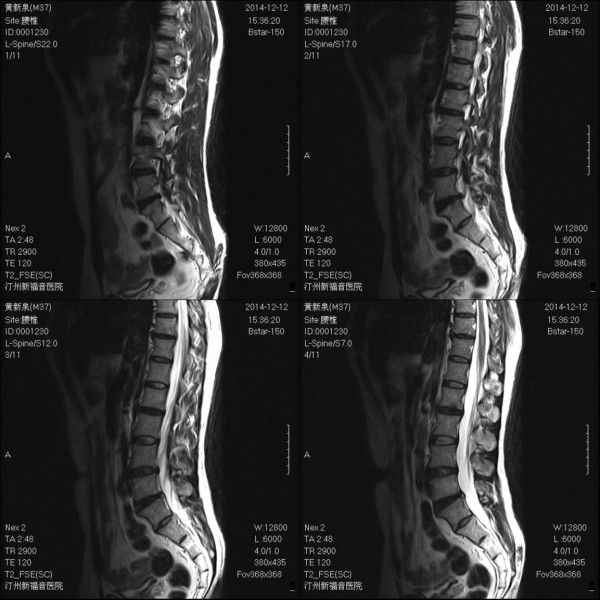

MRI6515:第三腰椎水平是不是囊肿 ?

在椎管内?

不好说

只是带入一二层,还是局部做一下比较好。